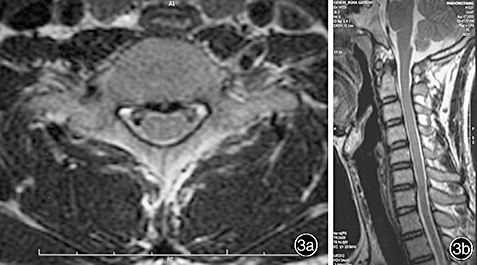

The images below are from just three of the many published case studies showing severe bulging discs in the neck and lower back that the nervous system was able to heal naturally:

Case Study 2: